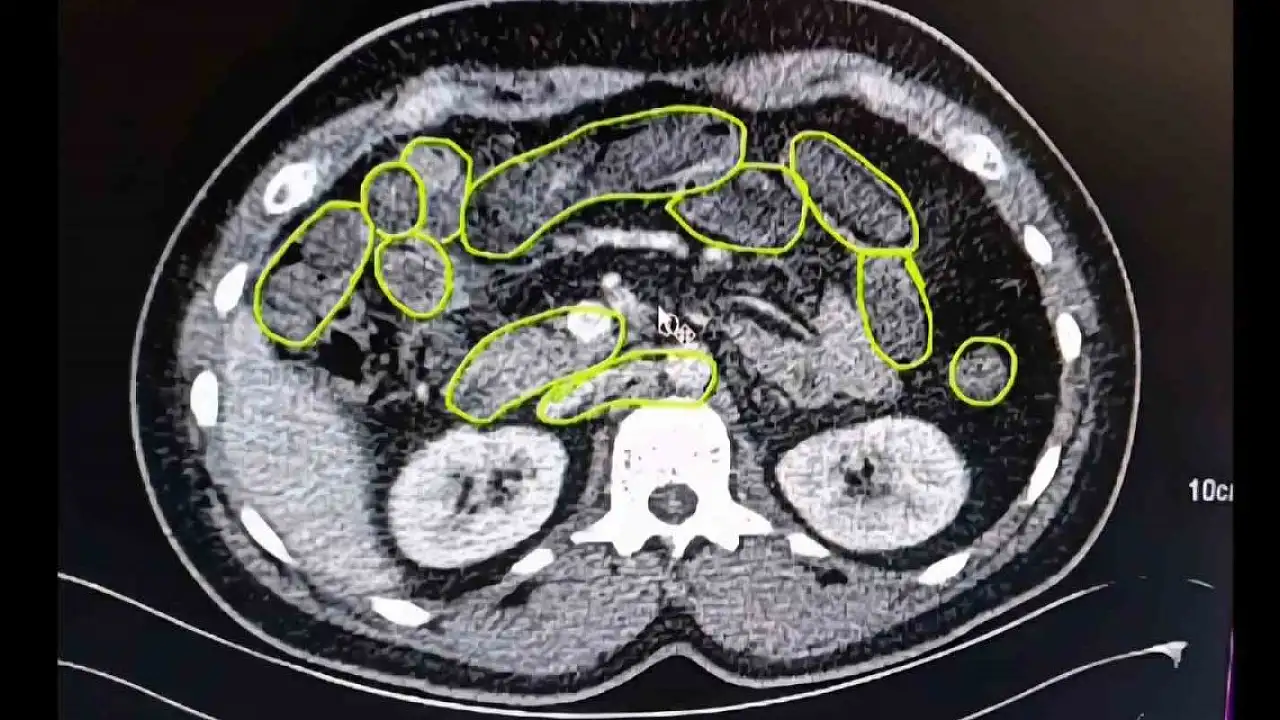

Şüphelilerin Kayseri Şehir Hastanesinde iç beden muayenesine alınırken, mide ve bağırsaklarında da çok miktarda kapsül şeklinde uyuşturucu olduğu değerlendirilen yabancı maddeler tespit edildi.